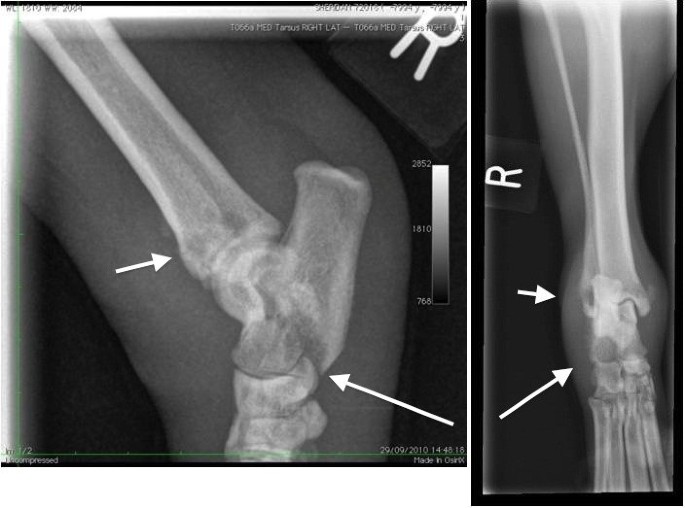

Radiographs of the right hock and thoracic spine showed focal areas of osteolysis and new bone formation within the dorsal arch of the axis, and in the distal 1 cm of the tibial diaphysis, distal fibula and the plantarodistal aspects of the body of the calcaneus (Figures 1 and 2). These findings were suggestive of a neoplastic or infectious process.

Mediolateral and dorsoplantar radiographs of the right tarsocrural joint. There are focal areas of osteolysis in the distal 1cm of the tibial diaphysis, distal fibula (short arrows) and the plantarodistal aspects of the body of the calcaneus. (long arrows). Proliferative active periosteal bone formation is present along the lateral aspect of the calcaneus and distomedial tibial diaphysis and cranio distal tibial diaphysis. A large soft tissue swelling encircles the joint.